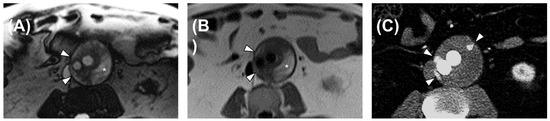

3.2. Morphological MRI Diagnostic Performance

3.3. Flow MRI Diagnostic Performance

4. Discussion